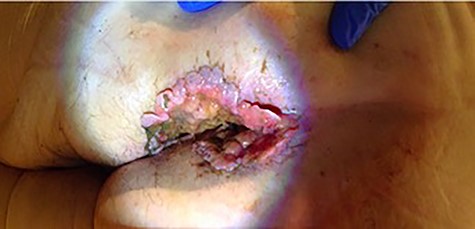

The perianal lesion encompassed the entirety of the anal margin. It had scalloped edges along the periphery of the lesion with a pale pink wound bed and associated mucoid drainage. There was no anorectal tenderness on exam but also no sphincter tone. The mass measured 11 × 6 cm with a 2 cm extension into the anal canal (Fig. 1).

Multiple 4-mm punch biopsies were obtained which returned as BCC with nodular and infiltrative patterns. A computed tomography of the chest abdomen and pelvis was obtained that showed no evidence of metastatic disease. A magnetic resonance imaging (MRI) of the pelvis (Fig. 2) showed extension into the anal canal with complete loss of the external sphincter muscle and a majority of the internal sphincter muscle.